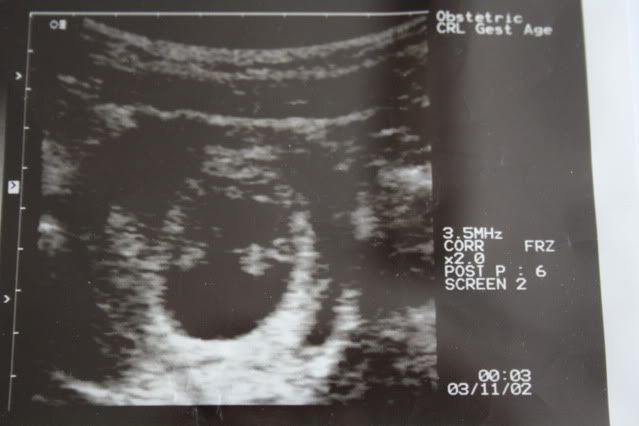

Er dette 1 eller 2?

1 baby

ser ut som det er to stk og at de er eneggede for ser ikke noe skille mellom dem....

Dette er i uke 8 :) Litt dårlig bilde men det var alt legen fikk til..Men glemte å spørr om det var 1 eller 2..

Helt klart to!!!

Ser ut som 2 [:)]

Jeg og fikk en liten ide om at det kunne være 2..Men sånn som jeg har blitt forklart nå så er babyen den hvite på høyre side og morkaken på venstre side.. :)